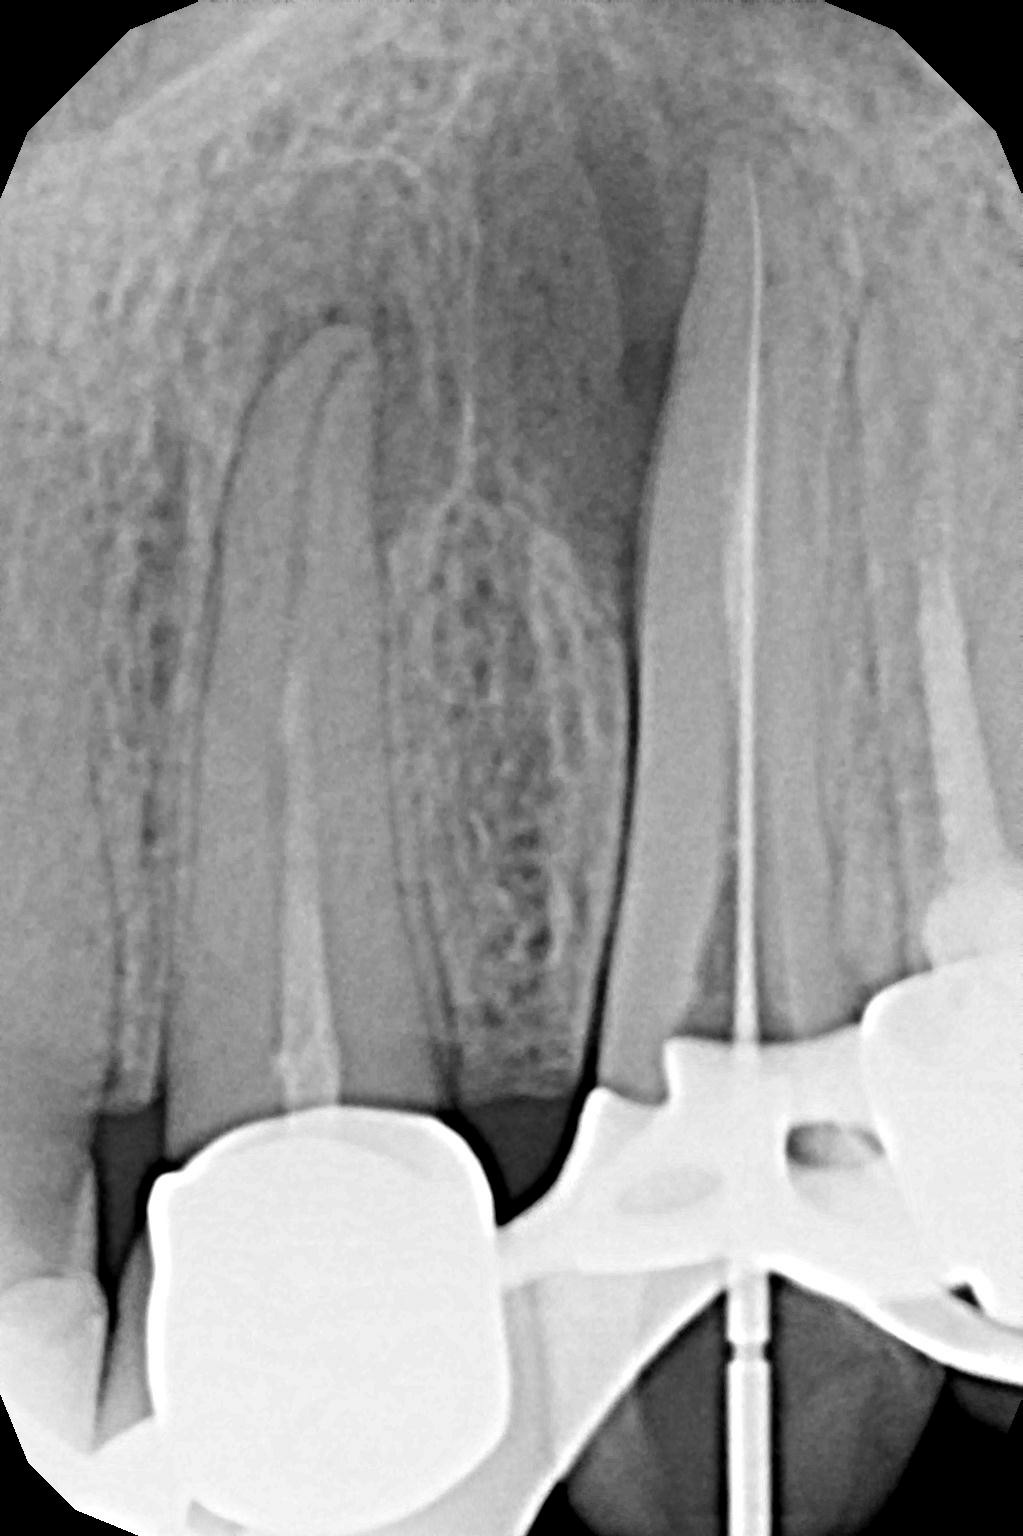

W przypadku zaawansowanych postaci zapaleń miazgi oraz zapalenia tkanek okołowierzchołkowych obraz radiologiczny jest warunkiem rozpoznania. W takiej sytuacji standardem diagnostycznym są zdjęcia przylegające zęba, często wykonywane przy użyciu radiowizjografii na fotelu stomatologicznym w trakcie leczenia zęba. Przydatne jest również badanie RTG OPG pantomograficzne, które pokazuje w dwuwymiarowym obrazie zarówno uzębienie, jak i cały układ kostny szczęki oraz żuchwy.

Stożkowa tomografia komputerowa CBCT, ze względu na dokładne, trójwymiarowe obrazowanie 3D, bez zniekształceń ukazuje szczegóły anatomii zęba oraz okolicznych tkanek, wyjaśniając nierzadko problemy niemożliwe do zdiagnozowania standardowymi metodami.

Podstawowym narzędziem diagnostycznym podczas leczenia jest endometr, elektroniczny miernik długości kanału, którym w trakcie procedury wykonuje się pomiary oraz potwierdza stopień drożności kanału.

Na podstawie zdjęcia rentgenowskiego określa się kształt i długość kanału bądź za pomocą specjalnego urządzenia mierzy się jego długość. Potem lekarz otwiera wejścia do kanału, chroniąc ząb koferdamem, czyli specjalną gumą, zapewniającą sterylność oraz chroniącą przed środkami chemicznymi służącymi do oczyszczania kanału. Używa się do tego zarówno specjalistycznego sprzętu, jak i nowoczesnych mikroskopów, pozwalających na uzyskanie dokładnego obrazu leczonego zęba. Ostatnią czynnością jest wypełnienie materiałem światłoutwardzalnym i zabezpieczenie zęba przed dostaniem się i rozwojem bakterii mogących wywołać wtórny stan zapalny.